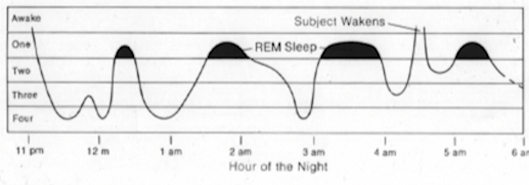

- 睡眠中各个阶段的脑电波

图9-2 - 睡眠周期

图9-3 - 正常人睡眠时一定有做梦

- 黑色的地方是正做梦的时候

深睡眠时做的梦记不得,浅睡眠时做的梦会短时间记得,久了也会忘记,这是一种保护机制,防止梦境和现实搞混。小孩子就容易发生搞混的事情。